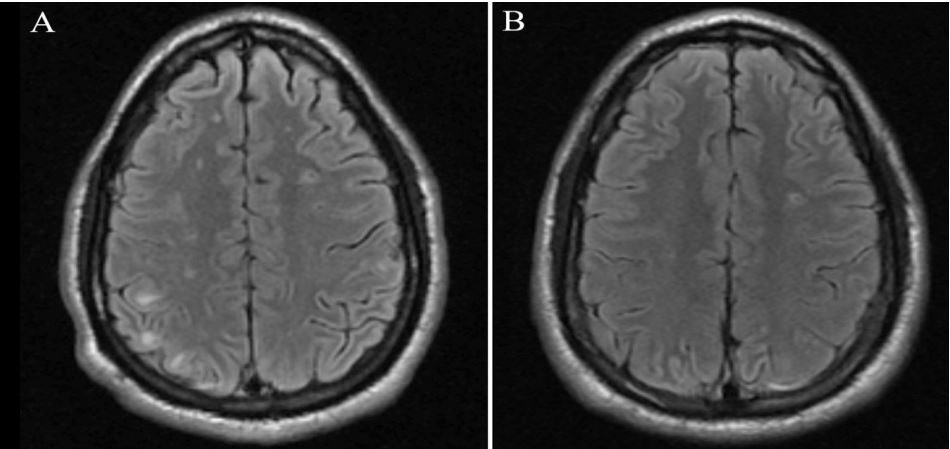

Computed Tomography (CT) of the chest showed a consolidation within the lingula with extension into the anterior chest wall, and a 2 x 5.7 cm soft tissue chest wall fluid collection (Figure 2). Magnetic Resonance Imaging (MRI) brain showed innumerable enhancing intraparenchymal and leptomeningeal/ependymal lesions and enhancement within the right mastoid and below the skull base (Figure 3A). On second night of hospitalization, he developed a fever of 102.3o F. After chest wall abscess was aspirated, he was started on isoniazid, rifampin, pyrazinamide, ethambutol, azithromycin, linezolid, cefoxitin, amikacin and dexamethasone for suspicion of possible mycobacterium infection. Chest wall lesion was also biopsied, and preliminary pathology review showed foamy histiocytes and no granulomas. Transthoracic and transesophageal echocardiogram revealed a small mitral valve vegetation. Culture from chest wall aspirate grew a Gram-positive rod anaerobe after 6 days of incubation, subsequently identified as Actinomyces meyeri by Matrix-Assisted Laser Desorption/Ionization-Time of Flight (MALDI-TOF) mass spectrometry. Fusobacterium necrophorum (beta-lactamase negativefi) also grew on culture and later identified. 16S ribosomal RNA testing showed minor abundance of Aggregatibacter actinomycetemcomitans, Fusobacterium nucleatum, Ralstonia pickettii, Methylbacterium radiotolerans, Caulobacter spp, Novosphingobium spp, and Pseudomonas japonica. Final pathology review of chest wall lesion showed acute and chronic inflammation with prominent histiocytic infiltrates. Gram, acid-fast bacillus, Fite, Giemsa, and periodic acid-Schiff stains did not reveal any microorganisms.

His antimicrobials were changed to high dose intravenous ceftriaxone (2 gm every 12 hours). Metronidazole was added but discontinued after 8 days due to pruritis and lack of beta-lactamase positive anaerobes identified on cultures. Positron Emission Tomography (PET) scan confirmed disseminated disease with fluorodeoxyglucose avid foci in the left temporal lobe of brain, multiple subcutaneous nodules in the neck, chest, abdomen, pelvis and both upper and lower extremities, and airspace consolidation in the anterior left upper lung lobe extending to the adjacent mediastinum and left anterior chest wall. After 6 weeks, his chest wall abscess had significantly improved with resolved lesions on MRI brain (Figure 3B), and he was switched to high dose oral amoxicillin with plan to complete a 12 month treatment course.